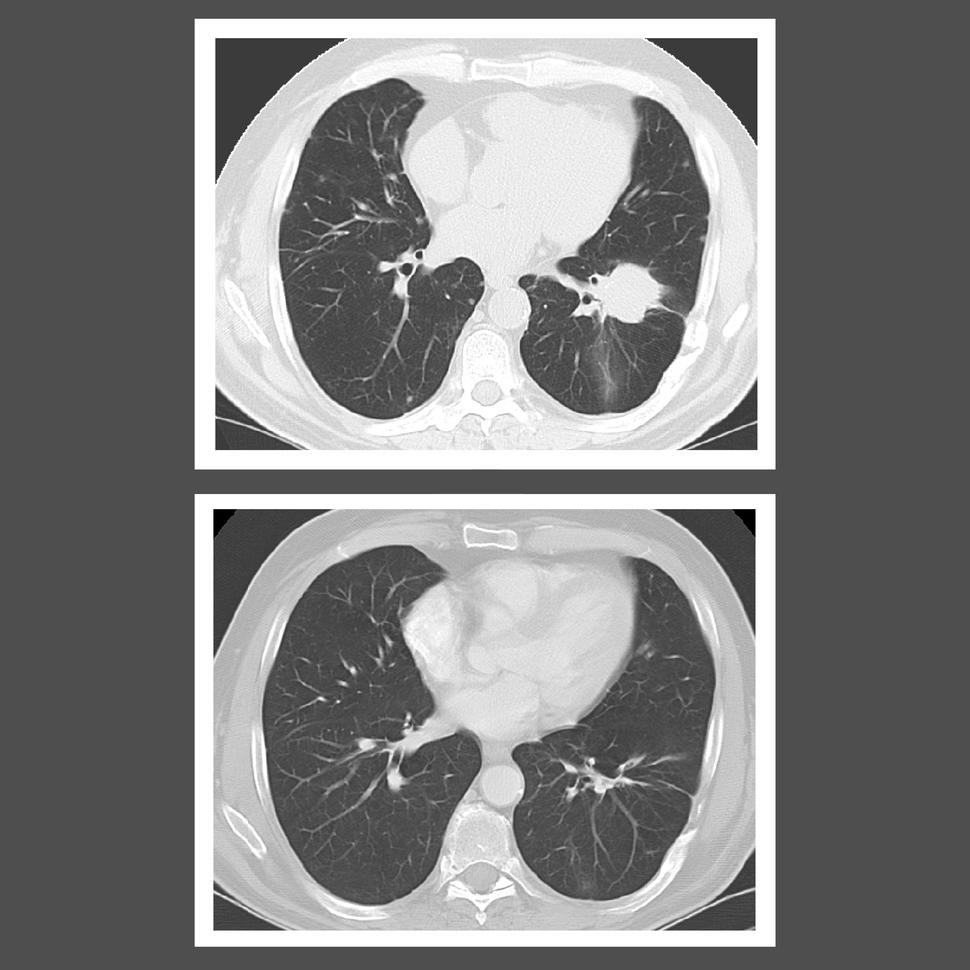

CT scans of a patient before (top) and after (bottom) treatment with interferon alfa-2b. After treatment, the large lesion in the right lung disappeared.

Credit: National Cancer Institute